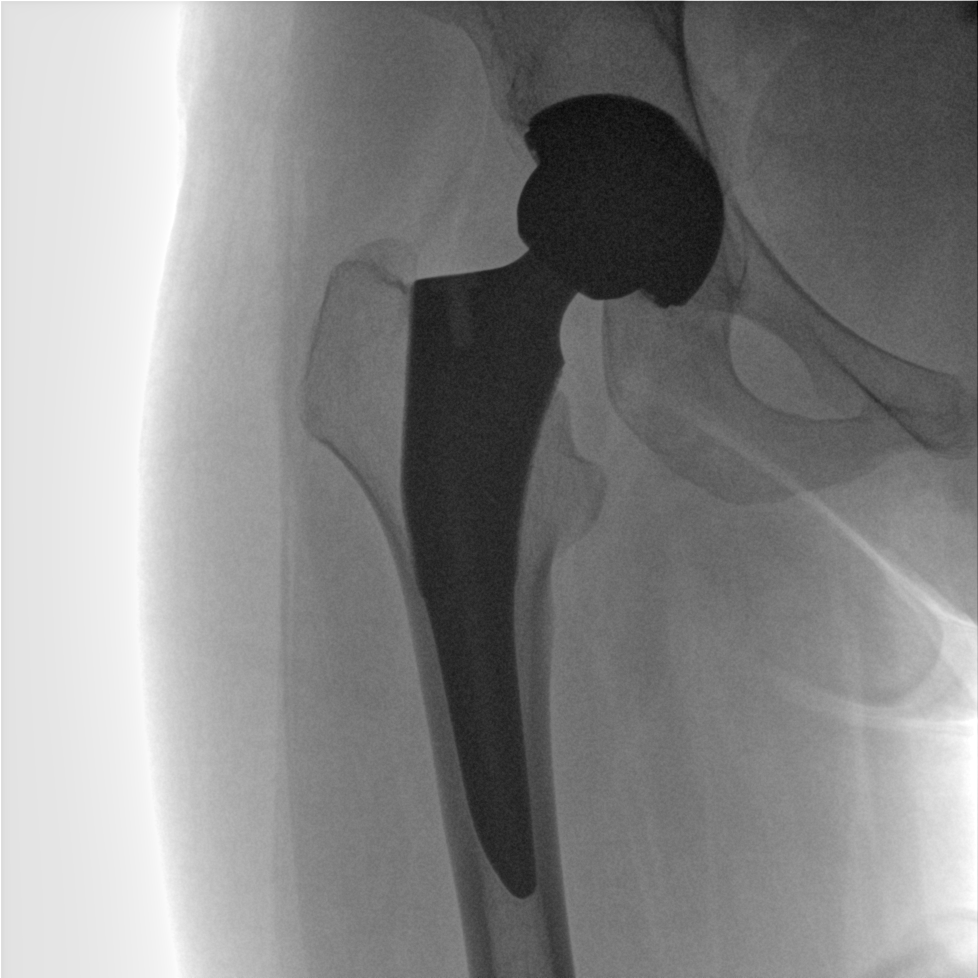

術(shù)中三維成像和橫斷面圖像提供多角度的手術(shù)診斷信息,輔助醫(yī)生進行術(shù)中評估判斷,諸如骨折復(fù)位情況和內(nèi)植入螺釘?shù)某叽绾臀恢?,輔助手術(shù)更好地完成。

提供更大的術(shù)中三維成像視野,采集更多圖像信息,可一次拍全全段頸椎、全段腰椎、七節(jié)胸椎、雙側(cè)骶髂關(guān)節(jié)、股骨頭及單側(cè)盆骨。